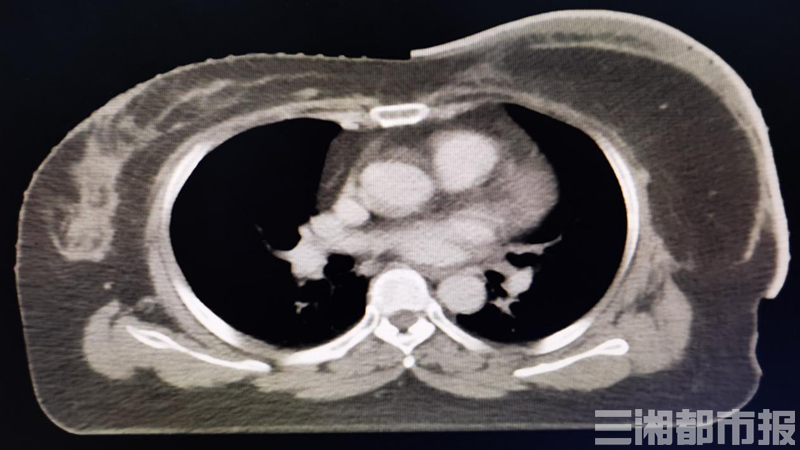

(实施3D打印组织补偿物技术实例)